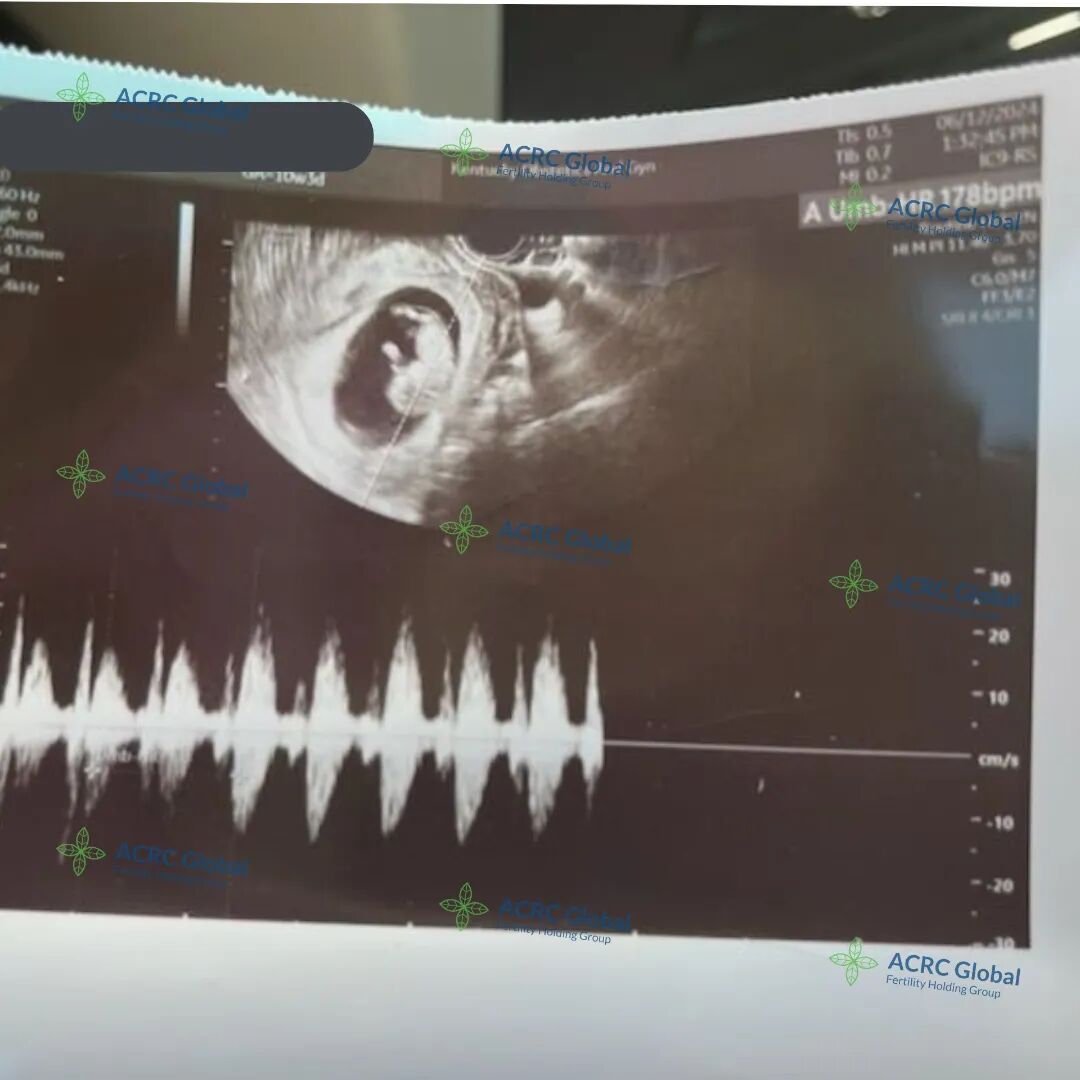

爱妈S在首次B超检查来了!已能听到宝宝强有力的心跳,尽管宝宝还很小。准父母对此感到无比激动,他们特别期待属龙的宝宝,并已成功匹配了两位代母,另一位爱妈的妊娠也在顺利进行中,满怀期待宝宝们继续健康成长。